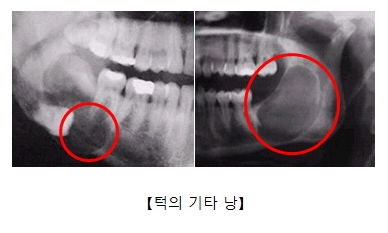

턱의 기타 낭증(Other cysts of jaw)

관련질환

치근낭

관련용어

아래턱